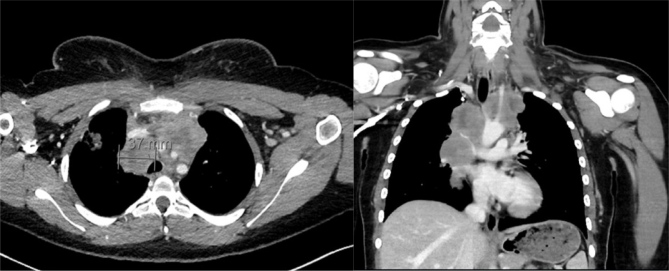

An 18-year-old woman presented to her general practitioner with a history of non-itching facial swelling, erythematous skin rash and a slightly coarse voice for a few days. She denied dyspnoea, B-symptoms and pain. Physical examination revealed generalized facial and neck swelling not involving the tongue or the oral mucous membranes. There was no lymphadenopathy. These findings resulted in the diagnosis of allergic angioedema and in oral treatment with corticosteroids and antihistamines. The swelling responded partially but reoccurred with dose reduction of the corticosteroids. Outpatient referrals to a dermatologist, an endocrinologist and a rheumatologist resulted in confirmation of the diagnosis of allergic angioedema, suspected iatrogenic Cushing syndrome and possible connective tissue disease, respectively. Three months after the first outpatient presentation the patient was admitted to our hospital with severe fatigue and left-sided chest pain. The clinical examination showed the known facial and neck swelling- and a sinus tachycardia (120 bpm) without any fever. Furthermore, the neck swelling seemed to be slightly asymmetrical. This was accompanied by leucocytosis, elevated C-reactive protein, and lactate dehydrogenase. An electrocardiogram showed sinus tachycardia (120/min) with a S1Q3-type. An ultrasound of the neck showed thrombosis of the left jugular vein. Subsequent computed tomography scan of the chest revealed a large mediastinal mass causing acute superior vena cava syndrome. Mediastinal large B-cell lymphoma was confirmed by biopsy. The patient underwent six cycles of DA-R-EPOCH (rituximab, etoposide, prednisolone, vincristine, cyclophosphamide, doxorubicin). Treatment resulted in complete response.

Abstract Image